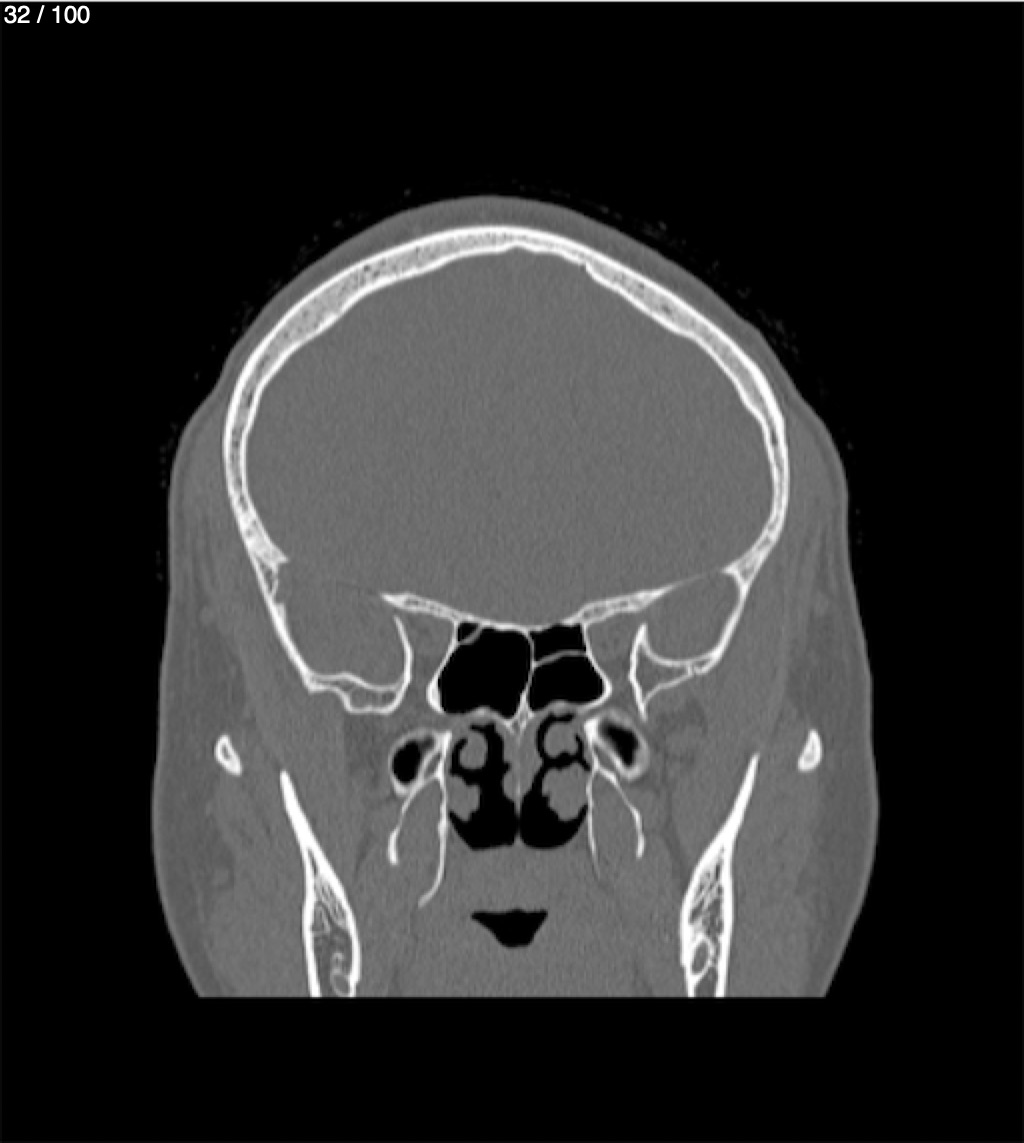

Yonelly Barrios Diaz 35A - T.C Craneo